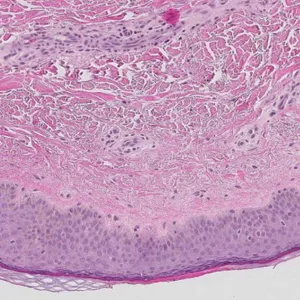

Livmorhalskreft

- "Who are at risk of developing cervical cancer?" Utvikling av nye biomarkører som kan forutsi hvilke kvinner som har risiko for å utvikle livmorhalskreft. Fokus på immunforsvar og genetiske endringer i vevet. Samarbeidsprosjekt med Kreftregisteret og Sørlandet sykehus.